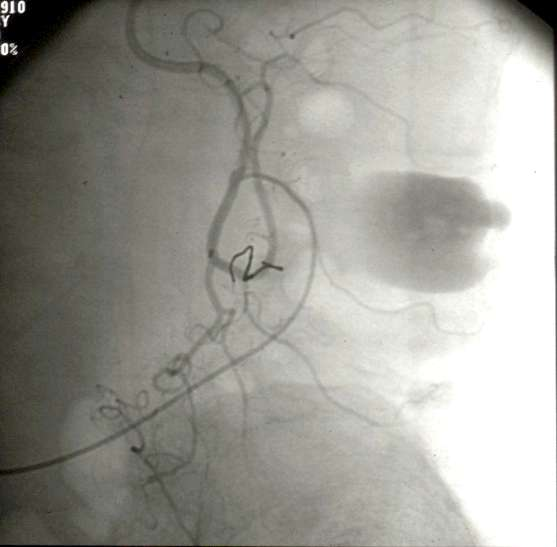

乙状结肠出血:超越边缘动脉栓塞

结肠脾曲:癌出血(姑息性栓塞)